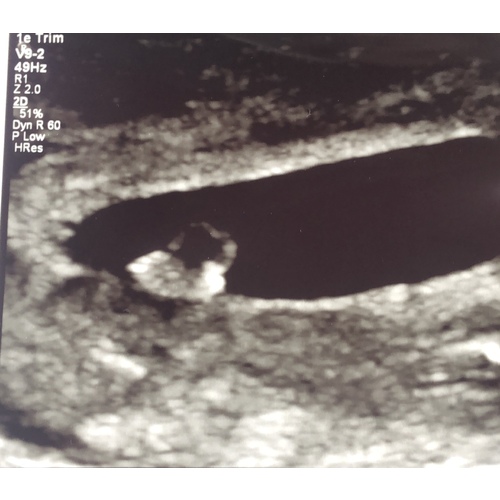

Met mij gaat het goed! Ik heb eigenlijk helemaal geen last van zwangerschapskwaaltjes.. in het begin was ik vaak aan het overgeven maar nu af en toe misselijk en kokhalzen. Verder alleen gevoelige borsten en sneller vermoeid (om 9 uur ben ik wel echt moe). Eerste echo was ook goed! Zie foto :). Merk wel dat soms de onzekerheid toeslaat.. Dat ik bang ben dat het gestopt is met kloppen maar dat zal iedere zwangere vrouw hebben. Volgende week weer een nieuwe echo! En misschien laat ik dit weekend nog een pretecho doen dan ben ik precies 8 weken. Hoe is het met jou? 鈽猴笍